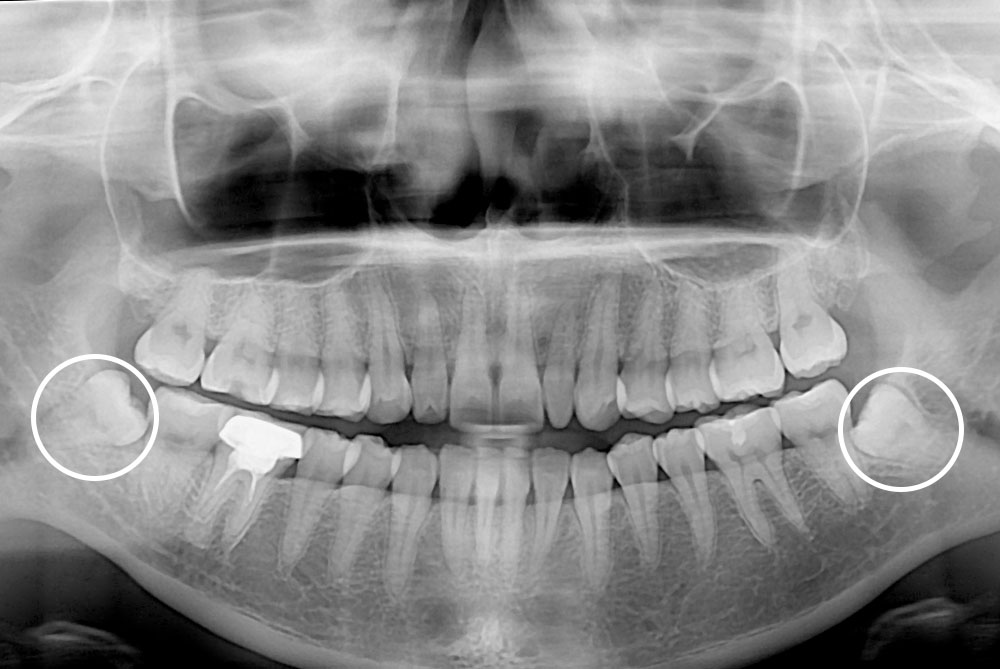

[사랑니] 매복 사랑니 발치

치료후 : 2018-03-16

세종치과는 구강악안면외과학 박사이신 원장님이 발치하는 치과입니다.